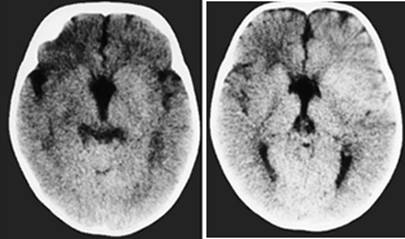

Figure 1

Clinical and image aspects of patient 1